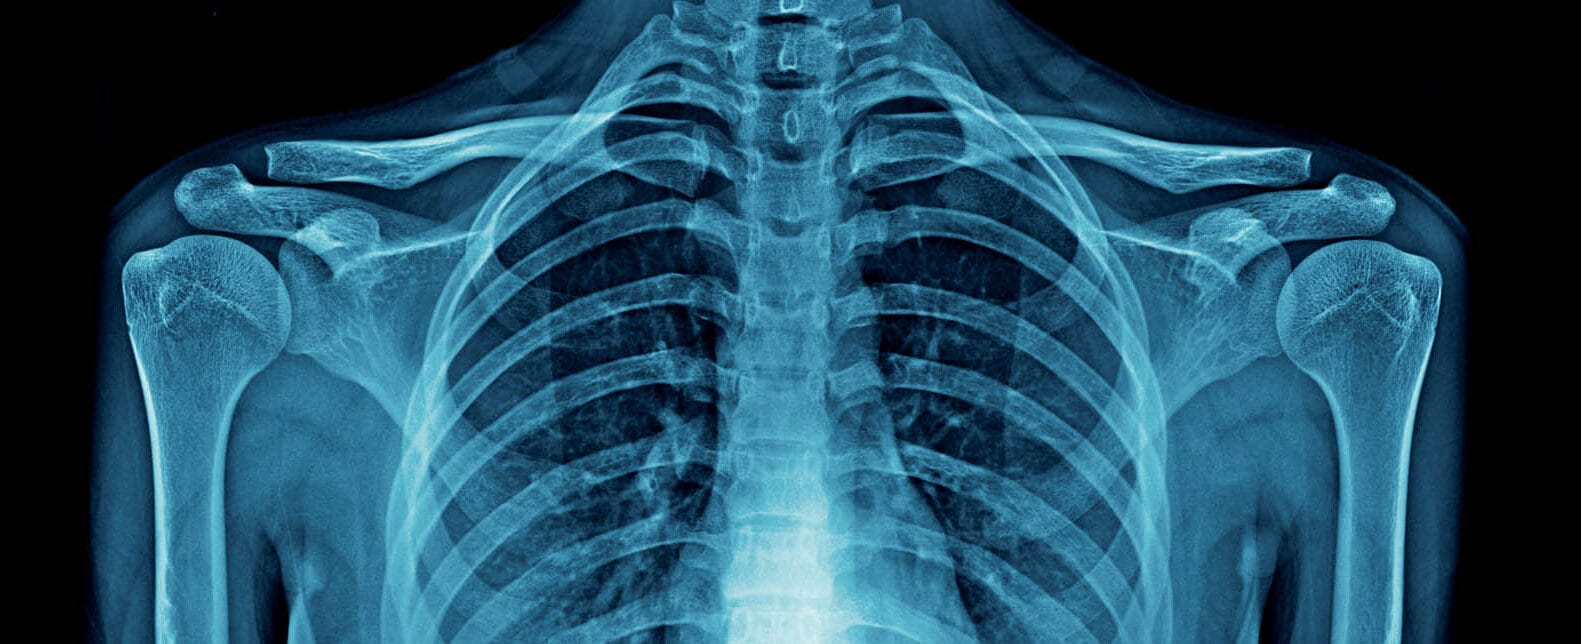

Discover the true potential of your biomaterial with X-rays

BoneSupport AB and scientists from Lund University used X-ray tomography to observe how the bone substitute produced by the company behaves inside the bone. They confirmed the distinctive features of the product and observed how it protects the bone material during mechanical loading.

BoneSupport AB develops biomaterials to be injected in bones and used as bone substitutes in patients. The company seeks to better understand how the biomaterial behaves and interacts with the bone during mechanical loading, and how the bone response is altered when combined with the biomaterial. Taking advantage of synchrotron X-ray’s high resolution, BoneSupport conducted experiments that showed an increased plasticity in samples where the bone is reinforced with their proprietary biomaterial. This evidence helps the company understand the features of the bone substitute once inside the bone and is valuable for future product development.

How does the biomaterial behave once injected in the bone? How does it interact with the native bone material? Does it improve the bone response to mechanical stress? Answering these questions involves understanding how the bone and the biomaterial interact during mechanical loading (which is the application of physical pressure to the point where the material fails). To tackle this challenging task, BoneSupport is collaborating with researchers at Lund University. The team turned to synchrotron-based X-ray tomography, which allowed them to carefully observe increasing stresses and their consequences in the biological structure. These experiments showed that the biomaterial produced by BoneSupport absorbs the loading in place of the native bone structure, thus helping the bone to better withstand mechanical stress.

The group of researchers from BoneSupport and Lund University aimed at understanding how differently a native bone and a composite of bone and biomaterial react to loading, where does the crack start, how does it propagate, and at what point does it fail. Synchrotron light is the only source of X-rays powerful enough to allow such experiments in a reasonable time frame, thanks to its higher resolution, better signal-to-noise ratio, and faster data acquisition rate. At the Swiss Light Source (PSI), the team performed high resolution tomography with in situ mechanical loading. They gathered a pool of human bone samples, injected half of it with the biomaterial, and left the other half in its native state.

The composite samples showed a more plastic behaviour, increased peak force, stiffness, and absorbed energy. The company also observed that the biomaterial seems to absorb most of the mechanical load leaving the bone largely intact until failure. The findings help BoneSupport understand how the biomaterial responds to loading inside human bone. This project also extended earlier collaborations between the company and Lund University to a new area of biomaterial characterisation.